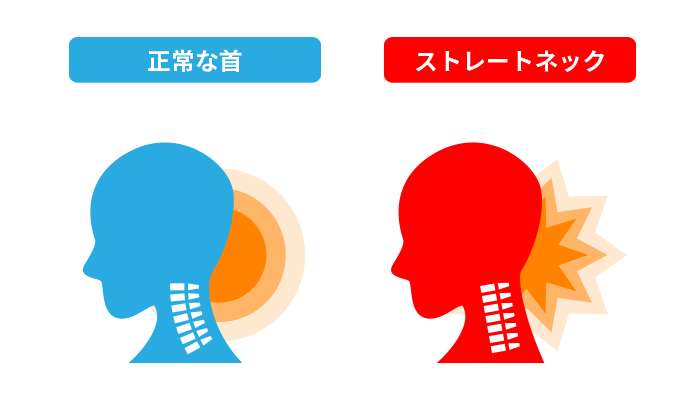

では、まず始めにストレートネックの原因を知るためにも、正常な首とストレートネックの違いを比較していきましょう。

正常な首は、首の骨がカーブを描いているのに対し、ストレートネックの状態は右図のように真っ直ぐで、カーブしていないことが分かりますよね。

正常な首の場合、7つの骨がカーブしたように積み重なっており、前弯に並んだ首の骨がそれぞれクッションの役割をし、頭の重さを上手く分散させています。

日常的に、歩く、または走る時には、足からくる衝撃が背骨を通って頭に伝わりますが、その時の衝撃を吸収し緩和するのが、首の骨のカーブの役割なのです。

一方、ストレートネックの場合ではどうでしょうか。

本来カーブを描いているはずの首が真っ直ぐの状態になっていますよね。

つまり、クッションとしての役割が機能せず、重力分散や衝撃吸収ができずに首周りの筋肉に負担が集中してしまう原因となります。

ストレートネックになることで、首周辺の筋肉や神経が圧迫され、首こりや肩こりを感じやすくなってしまいます。